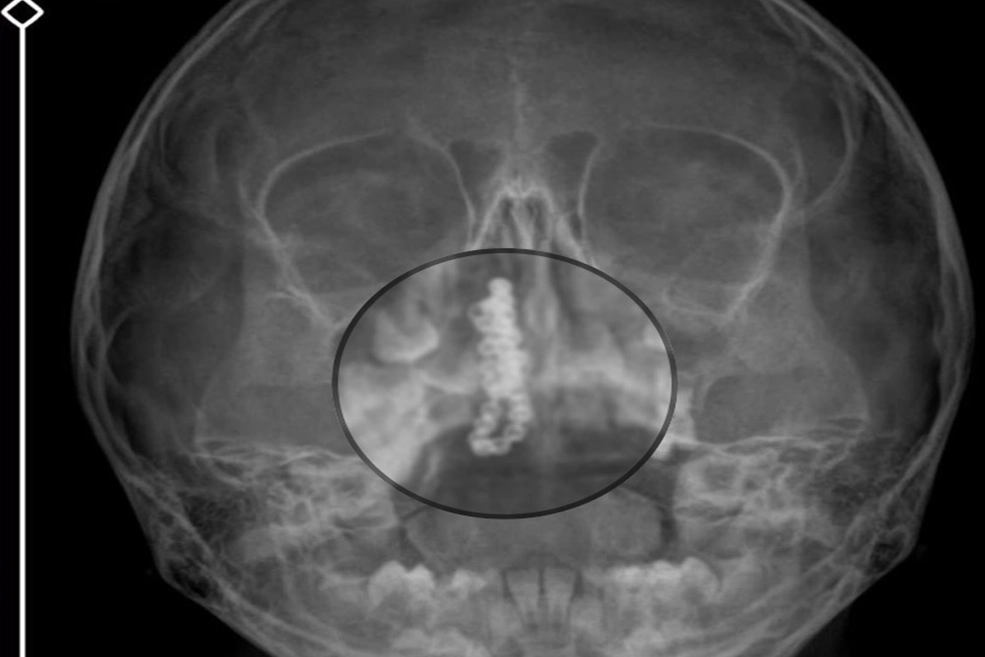

Kentte yaşayan Gökhan-Nalan Tekin çifti, yaklaşık 4 ay önce şiddetli burun kanamasının yanı sıra akıntı şikayetleriyle kızları Polen'i, bir özel hastaneye götürdü. Burada röntgeni çekilip, tetkikleri tamamlanan küçük kıza, iddiaya göre enfeksiyon teşhisi konulup, ilaç verildi. Eve dönen aile, kanama ve akıntının geçmemesi üzerine bu kez Rize Devlet Hastanesi'ne giderek Kulak Burun Boğaz Polikliniği'ne başvurdu. Devlet hastanesindeki doktorun incelemesi ve kapsamlı röntgen çekilmesi sonrası Polen'in burnunda metal cisim olduğu fark edildi. 2 yıldır burunda kaldığı değerlendirilip, küçük top şeklinde tırnak makası zinciri olduğu belirlenen cisim, başarılı ameliyatla çıkarıldı. Bir süre tedavisi sürdürülen Polen, sağlığına kavuşunca taburcu edildi. Özel hastane yetkilileri, konuyla ilgili açıklama yapmazken; aile suç duyurusunda bulunacaklarını söyledi.

Kızının burnundan sürekli siyah renkte akıntı olduğunu anlatan Gökhan Tekin, "Çocuğumun burnundan kanama ile sürekli siyah akıntı geliyordu. Özel hastaneye götürdüm. Özel hastanede film çekildi, hiçbir bulguya rastlanılmadığı söylendi. O siyah leke de enfeksiyona dayalı olan bir şey olduğu bize söylendi. Eve geldik, akıntı sürmesi üzerine bu kez devlet hastanesine başvurduk. Burunda metal zinciri fark ettiler. Böyle bir ihmalkarlık olabilir mi? Özel hastaneye gidiyoruz, paramızla rezil oluyoruz. Zincir, 2 yıldır burnunda ve devletimizin hastanesinde iyi bir doktorumuz zinciri ortaya çıkarıyor, kızım ölümden dönüyor. Ben sonuna kadar bu işin peşini bırakmayacağım. Sonuna kadar hukuk mücadelesi vereceğim. Bu da diğer hastalarımıza ibret olsun. İşte, bakın koca bir zincir. 'Bulguya rastlanılmadı' deniliyor" dedi.

Kızının ameliyat sonrası durumunun iyi olduğunu söyleyen Tekin, "İnanır mısınız bize 'Evde soba mı yanıyor? Acaba kömür isten dolayı mıdır bu?' dendi. Böyle bir şey olabilir mi? Ameliyattan çıkan parmağım kadar zincir. Devlet hastanesindeki doktor da 'Bu nasıl gözden kaçılabilir? Böyle bir pozisyon nasıl görülmeyebilir?' yorumunda bulundu. Allah'a şükür olsun atlattık. Şu anda durumu, vaziyeti iyidir. Ben şuna inanıyorum doktor da bir şans işidir. Bakın paramızla özele gideriz ya hani bizde, daha iyi ilgilenirler. Oysa devlet hastanesindeki doktorumuz olayı meydana çıkardı" diye konuştu.